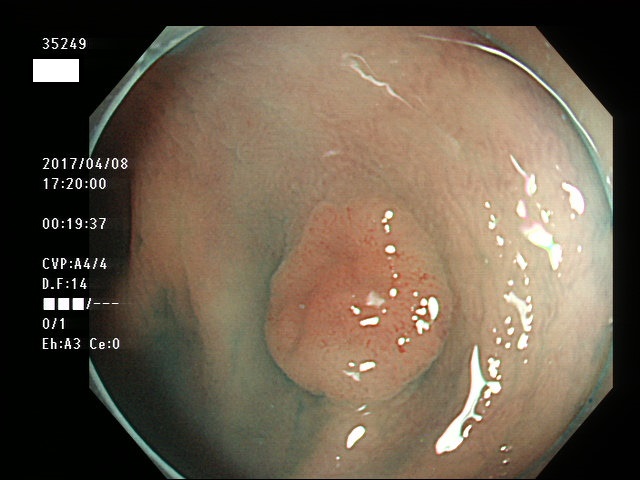

上記100名より抽出した平坦・陥凹型腺腫・SSAP(=癌化の危険が高いが見落としやすい病変)の内視鏡写真